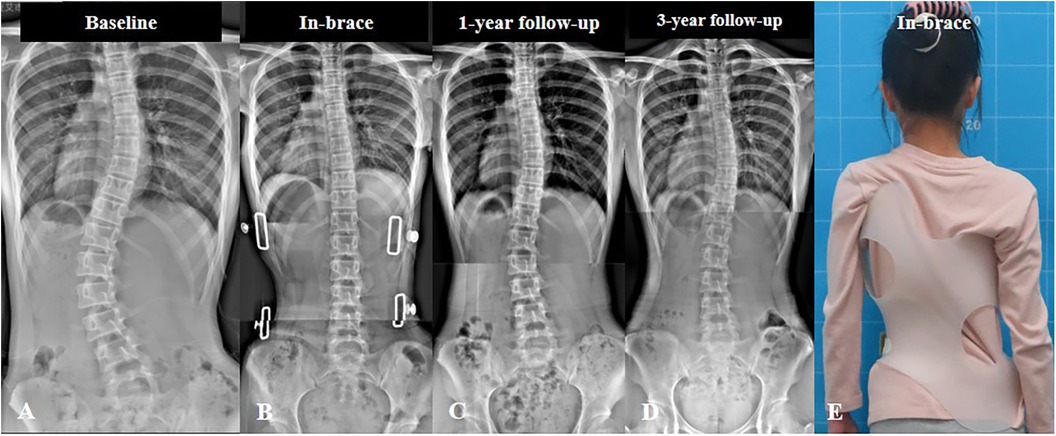

1. زاوية كوب (Cobb Angle)

يوفر الحزام الجديد فوائد إضافية في تحسين المظهر الخارجي للجسم.

2. تماثل الجذع وشكل الظهر

كانت الفروقات واضحة عند قياس تأثير الحزام على شكل الجسم:

الحزام الجديد حسّن شكل سطح الظهر بنسبة 49.6٪، وهو تحسن ملحوظ.

في المقابل، شهد مستخدمو الحزام التقليدي تدهورًا بنسبة 6.8٪ في شكل الظهر.

التماثل العام للجذع تحسن بنسبة 30٪ مع الحزام الجديد، بينما ازداد سوءًا بنسبة 2.2٪ لدى مستخدمي الحزام التقليدي.

وهذا يدل على أن استخدام القياسات ثلاثية الأبعاد يعزز التماثل العام للجسم بشكل واضح.